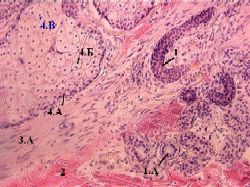

II. Типы себоцитов на препарате

2,г. Препарат - кожа с волосом ("тонкая" кожа). Окраска гематоксилин-эозином.

1. Здесь на уже известном нам снимке - несколько альвеол сальной железы.

2. Хорошо различимы разные виды себоцитов:

базальные (или камбиальные) клетки (4.А) - тёмные и относительно небольшие;

Полный размер

созревающие секреторные клетки (4.Б) - с увеличивающимся объёмом и всё более светлой и ячеистой цитоплазмой;

разрушенные клетки (4.В) - с плотными гиперхромными ядрами.